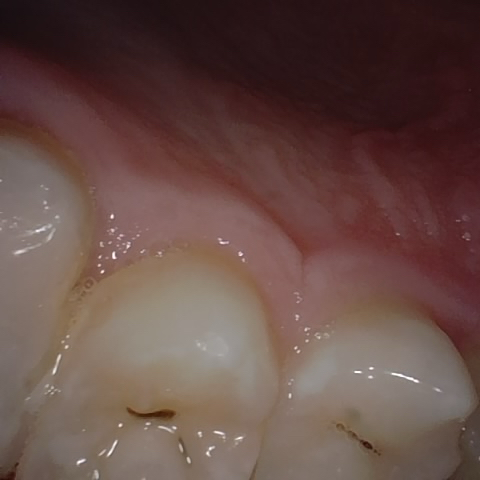

Annotated as "Good"